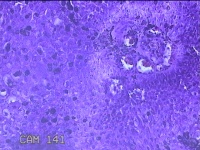

尿道口肿物

性别

男

年龄

46岁

临床诊断

尿道肿物

一般病史

发现尿道口肿物10余天。

标本名称

大体所见

灰白粉红色不规则肿物0.8x0.5x0.2一堆。

似有挖空细胞,有可能要考虑湿疣,片子这个效果,真是不敢猜。